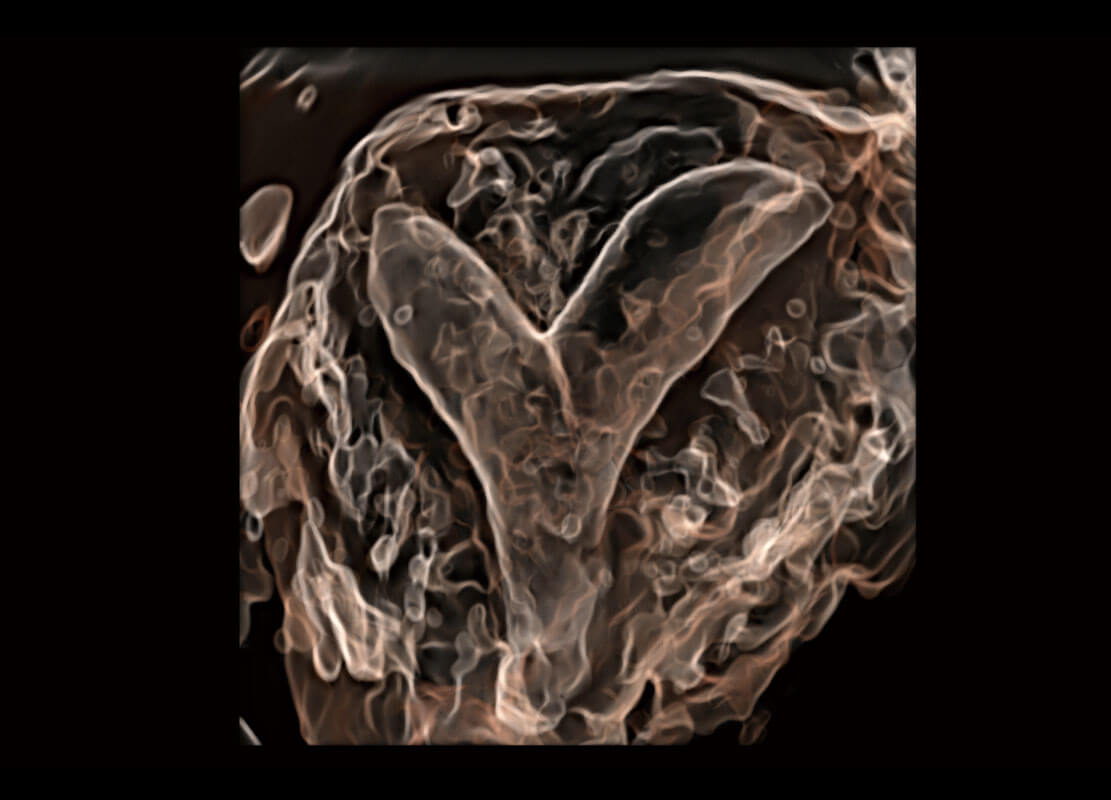

P60優(yōu)異的圖像質(zhì)量搭載專科探頭,在婦科基礎(chǔ)疾病的診斷、卵泡生長(zhǎng)的監(jiān)測(cè)、輸卵管通暢情況的判別等方面為您提供生殖應(yīng)用方案。

腔內(nèi)三維-宮內(nèi)節(jié)育器

腔內(nèi)三維-光影成像